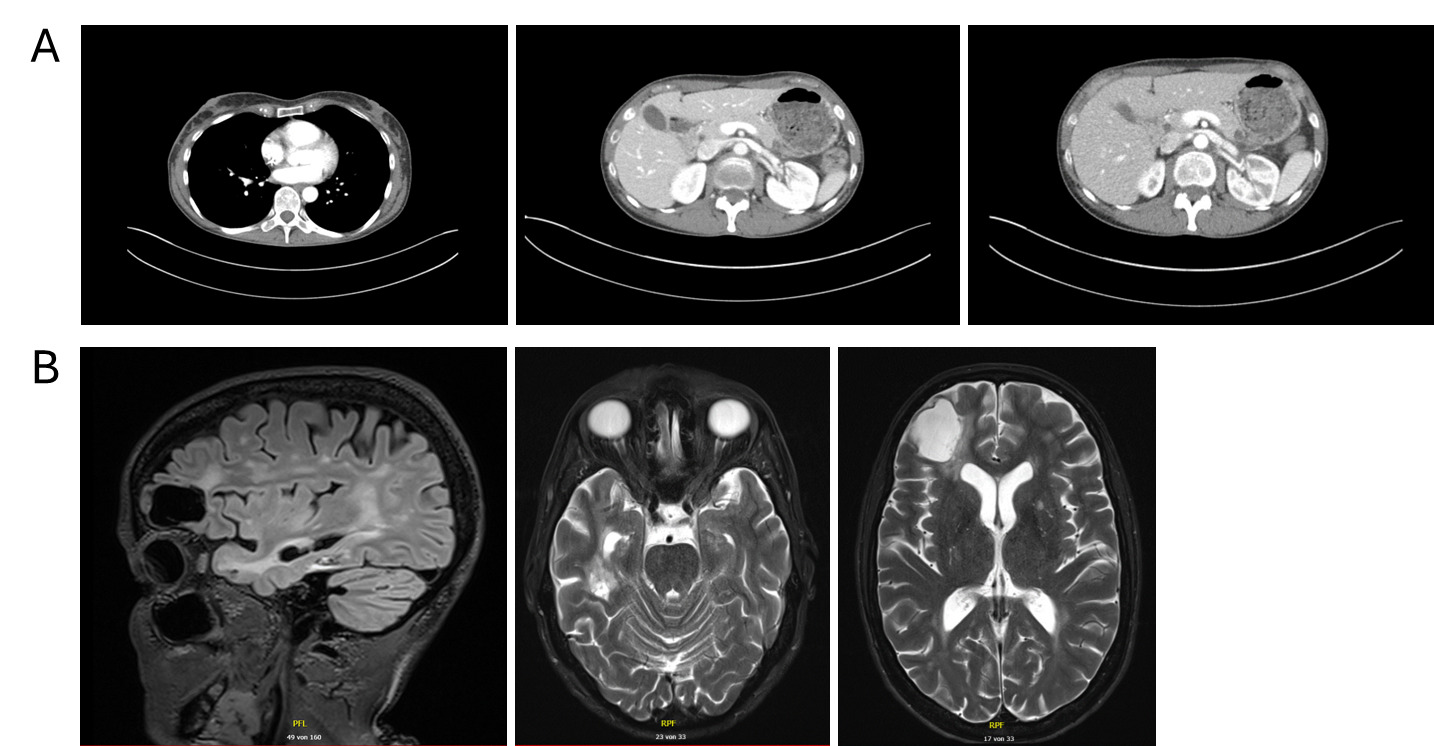

Restaging in September 2025 with contrast-enhanced CT of the thorax and abdomen and contrast-enhanced MRI of the brain demonstrated partial remission, with regression of systemic and intracranial disease and no new metastatic lesions (Figure 4). Therapeutic anticoagulation with apixaban was continued without any new thromboembolic events.

Comprehensive molecular profiling performed during ongoing treatment identified a pathogenic sBRCA2 splice-site mutation, enabling a biologically rational transition to targeted therapy with the PARP inhibitor olaparib. Importantly, olaparib was initiated after radiologic progression on chemoimmunotherapy rather than as maintenance following response, reflecting real-world treatment sequencing rather than trial-defined pathways. Under olaparib therapy, the patient again responded to treatment with regression of both systemic and intracranial disease and sustained clinical benefit with good tolerability. The intracranial response observed under PARP inhibition is clinically noteworthy, as many systemic agents demonstrate limited CNS activity, particularly in patients with a high baseline intracranial tumor burden who have already undergone whole-brain radiotherapy. Therefore, this case adds to the emerging real-world evidence supporting CNS activity and the feasibility of PARP inhibitors in BRCA-mutated TNBC.